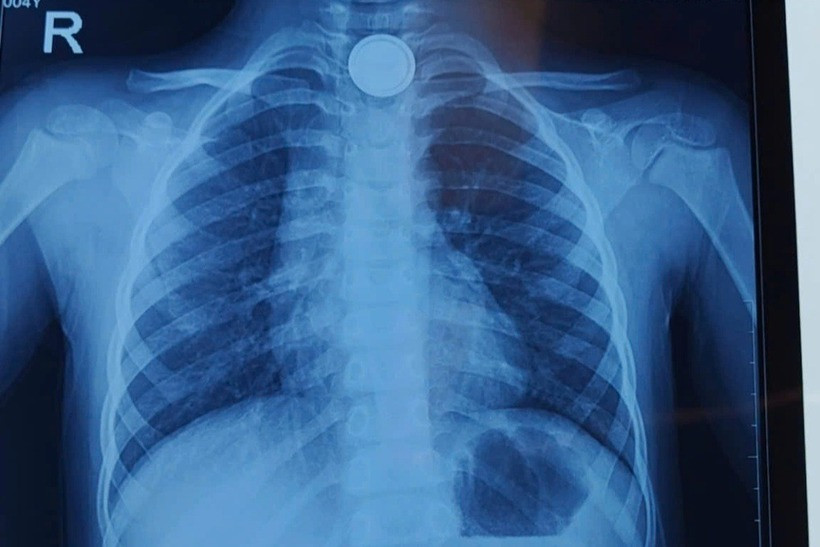

Cụ thể, 14h chiều ngày 8/3, bệnh nhi V. vô tình nuốt phải pin cúc áo. Gia đình nhanh chóng đưa bé đến bệnh viện gần nhà, chụp X-quang phát hiện dị vật pin mắc ở thực quản ngang mức xương đòn.

Vị trí pin cúc áo trong cổ bệnh nhi. Ảnh: Dân trí